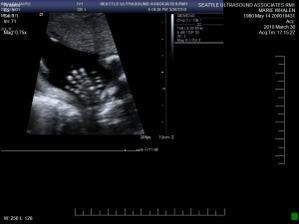

• 30.3. 2010 dalsi ultrazvuk v druhem trimestru odhalil zdrave miminko - je to chlapecek 🙂